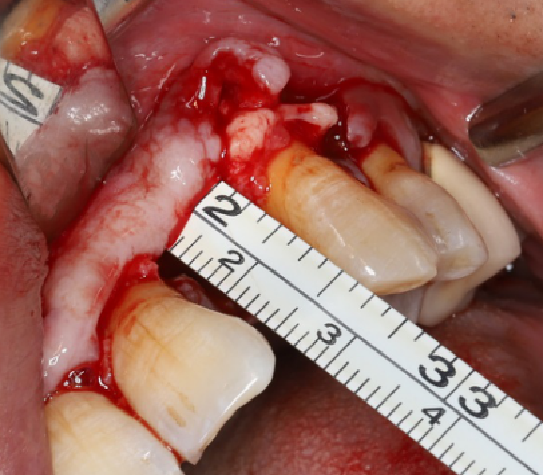

采用不切开骨膜的软组织扩张术——Soft Tissue Extend释放软组织张力

记录翻瓣后原始软组织瓣长度,使用软组织搔刮器(Soft Tissue Extender)冠根向搔刮软组织瓣。

在不切断骨膜的前提下,使用软组织刮治器反复搔刮软组织瓣,可以起到延长软组织瓣的作用。

使用软组织搔刮扩张前后对比:可见在不切断骨膜的前提下,使用软组织搔刮即可获得软组织瓣延长8-9mm。